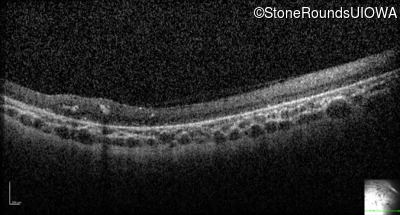

Optical Coherence Tomography - Right - Light Perception

Exemplar

Optical Coherence Tomography - Left - Light Perception